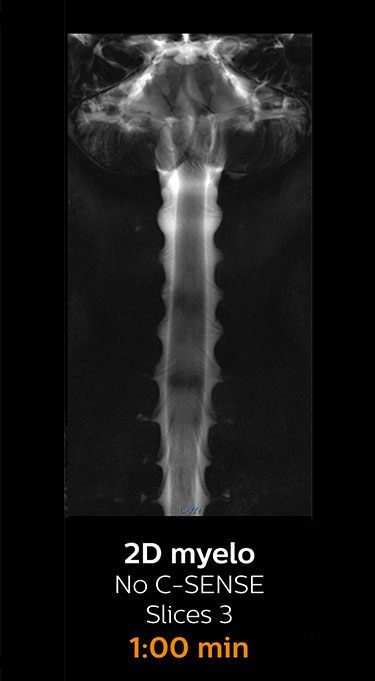

Fast MRI of cervical spine

With Compressed SENSE, the scan time for the routine cervical spine examination at KNC was reduced from 13:11 to 9:52 minutes, which corresponds to 25% reduction.

MRI examination of the cervical spine with Compressed SENSE

Ingenia 3.0T CX

Scan time 9:52 min. (was 13:11 min. without Compressed SENSE)